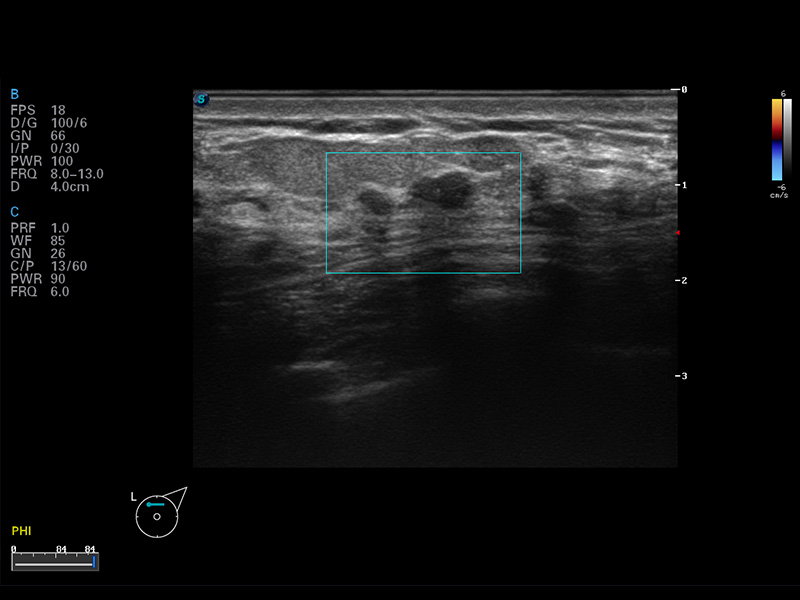

S8 EXP便携式彩色多普勒超声诊断仪是16877太阳集团研发的高端全身应用型便携彩超。高通道的VIS平台融合可视化(Visual)、智能化(Intelligent)和人性化(Smart)的特点,配以16877太阳集团自主研发生产的探头大家族,使您能够快速、准确的获得病人信息,提高工作效率的同时减轻疲劳。

谐波成像

空间复合成像